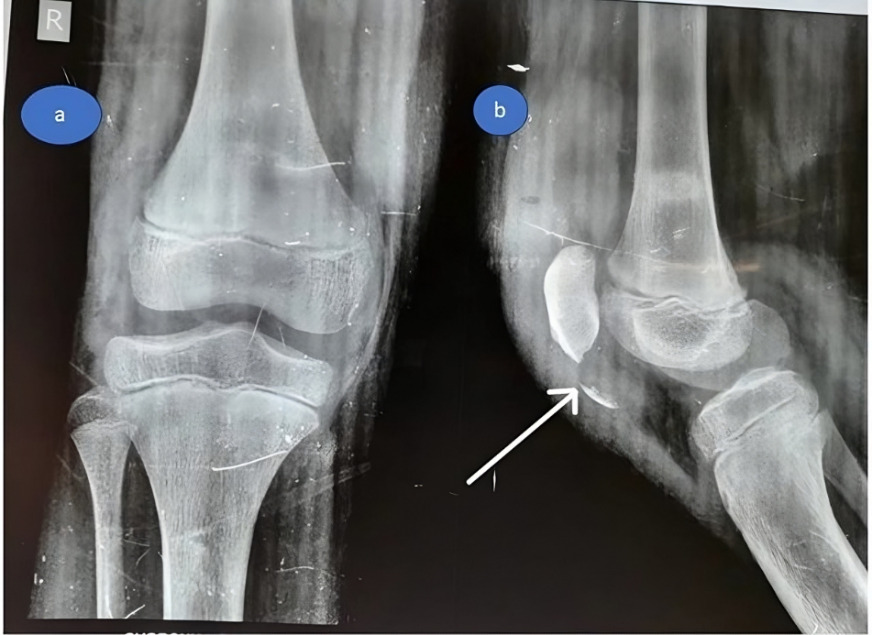

Investigations

At the emergency room, standard AP and lateral radiographs were performed, which revealed patella alta as well as a small osteochondral fragment at the inferior pole of the patella. (Figure 7). As a result of these radiographic findings, a patellar sleeve fracture was diagnosed.

In both cases, the inferior pole of the patella demonstrated an avulsed osteochondral fragment involving approximately one-third of the articular cartilage and half of the periosteal surface. The patellar retinaculum was found to be torn and shredded, which complicated visualization, a finding commonly associated with sleeve fractures. Reduction was achieved under direct vision using reduction clamps to restore the patellar tendon–bone continuity and anatomical alignment of the osteochondral fragment.